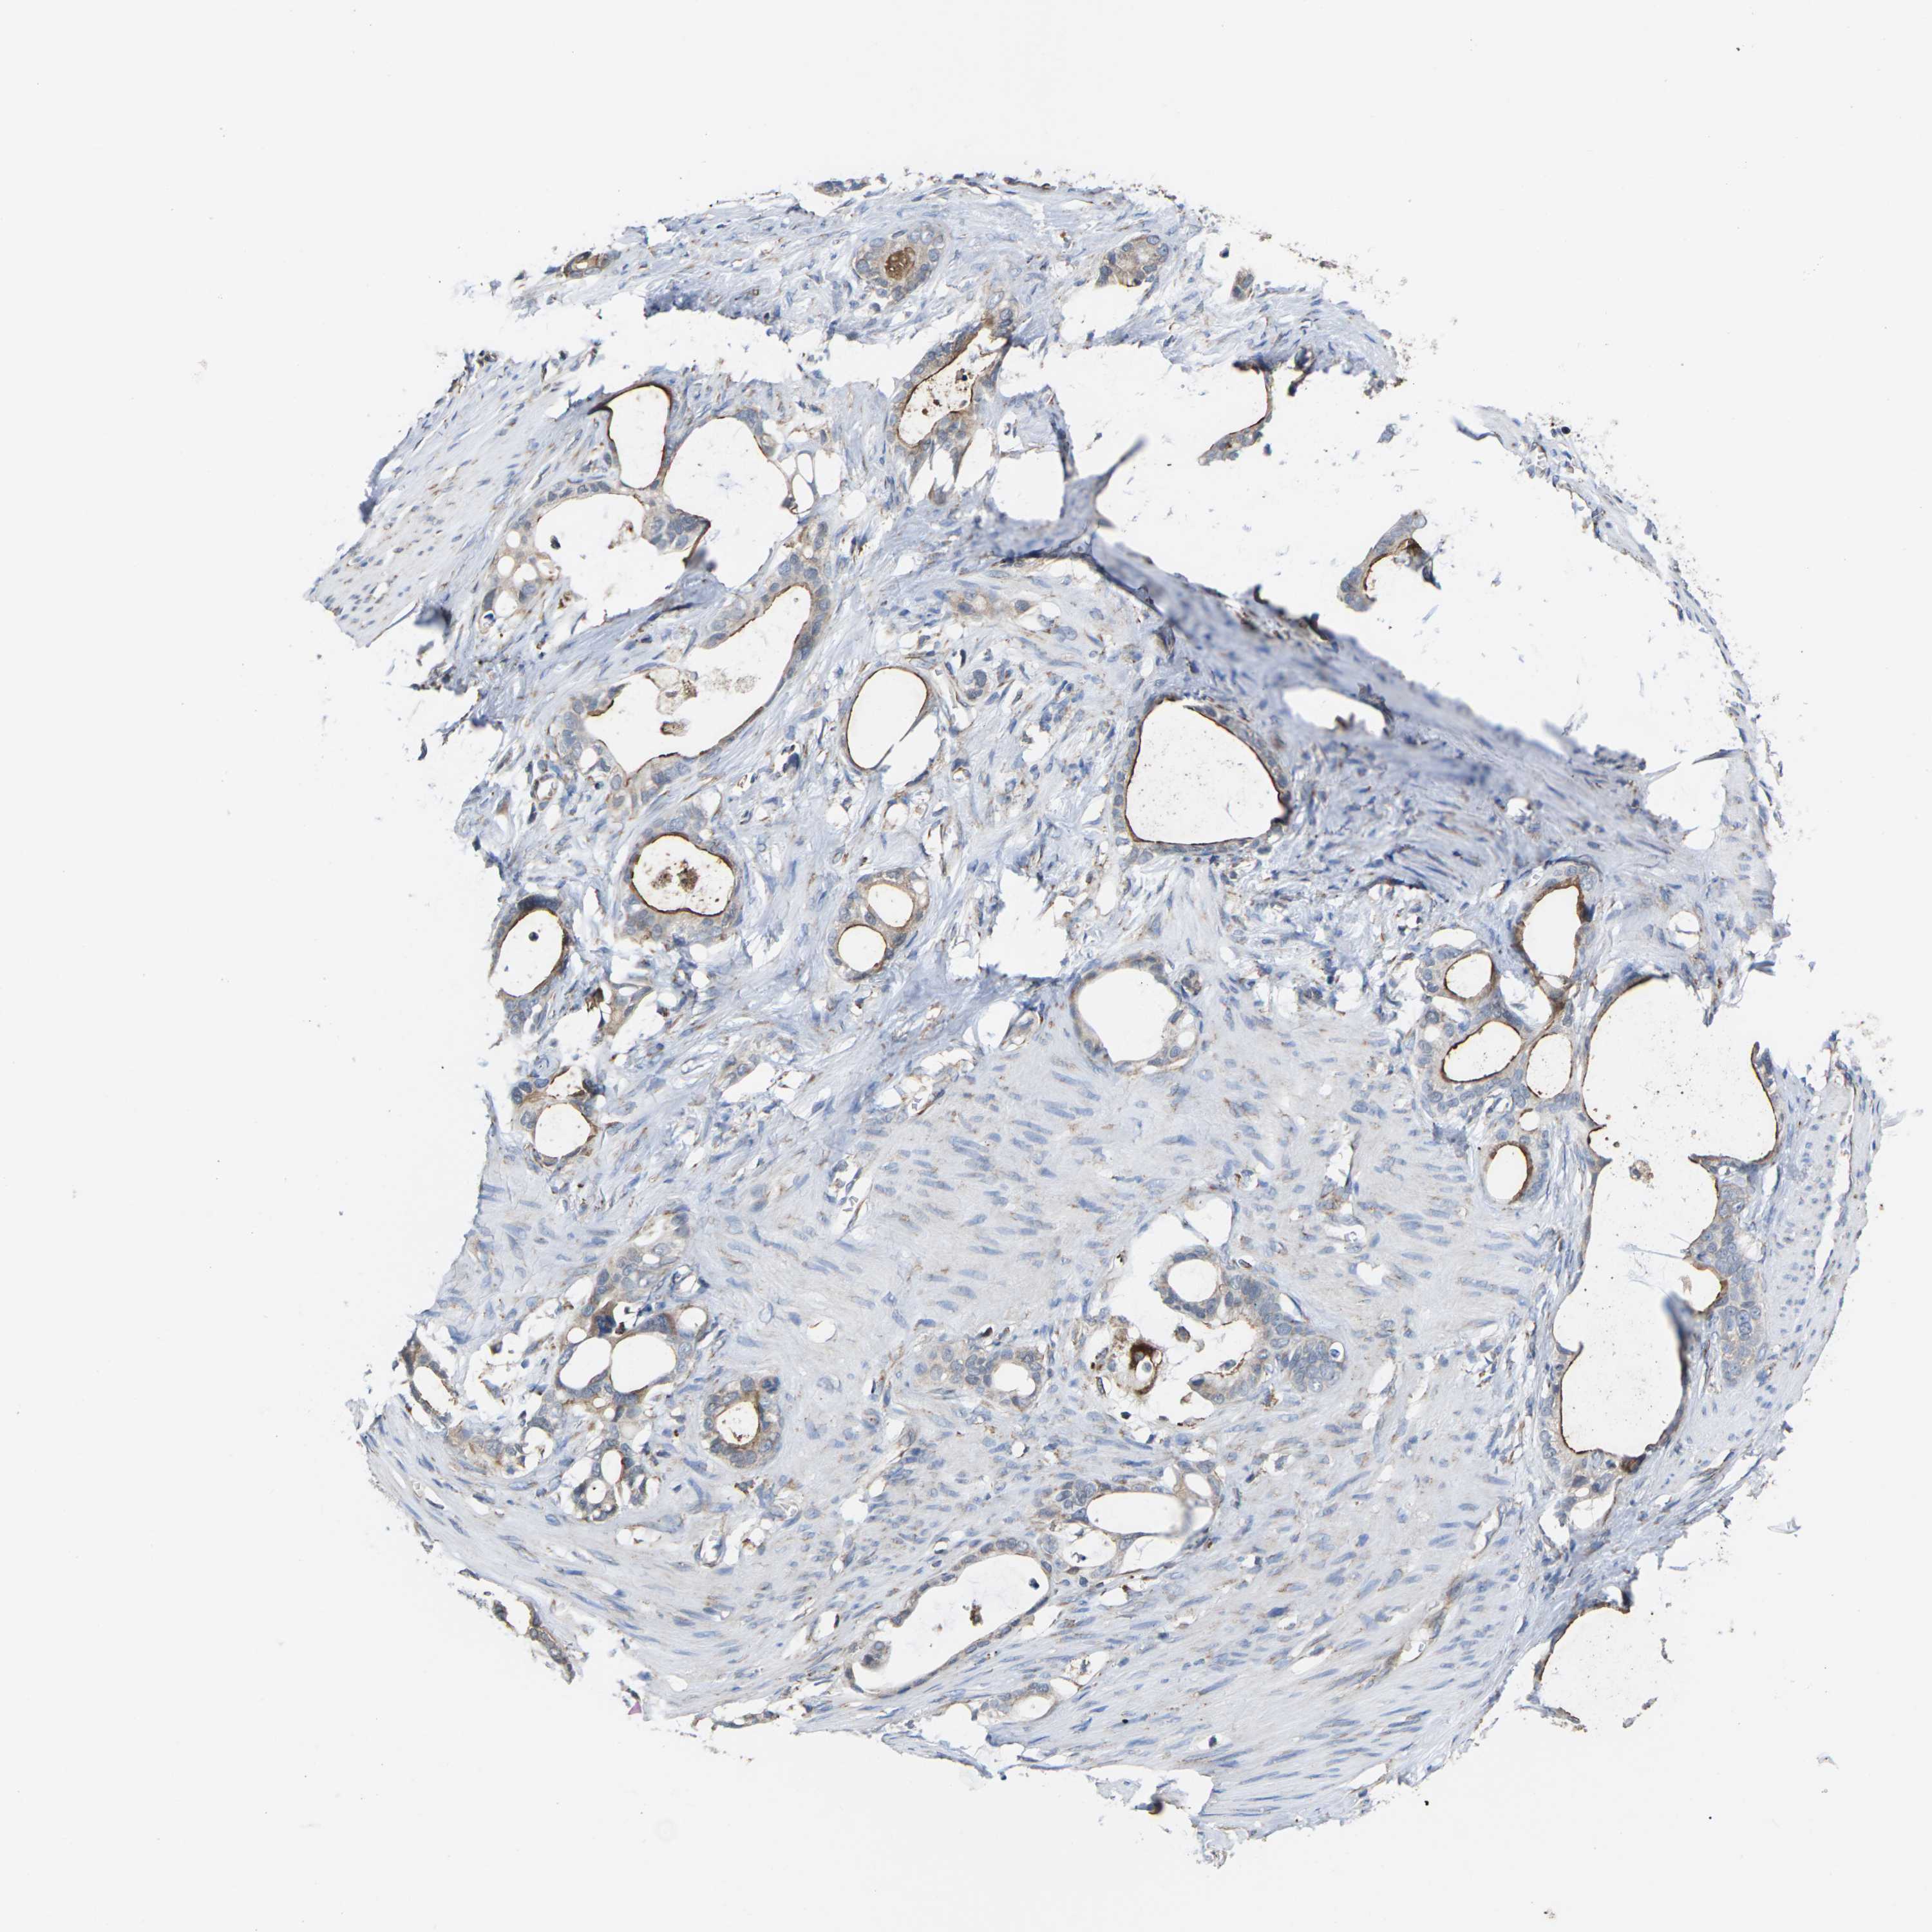

STOMACH CANCER - Protein expressioni

A mouse-over function shows sample information and annotation data. Click on an image to view it in a full screen mode. Samples can be filtered based on level of antibody staining by selecting one or several of the following categories: high, medium, low and not detected. The assay and annotation is described here.

Note that samples used for immunohistochemistry by the Human Protein Atlas do not correspond to samples in the TCGA dataset.

Antibody stainingi

Antibody staining in the annotated cell types in the current human tissue is reported as not detected, low, medium, or high, based on conventional immunohistochemistry profiling in selected tissues. This score is based on the combination of the staining intensity and fraction of stained cells.

Each image is clickable and will lead to virtual microscopy that enables deeper exploration of all samples and also displays staining intensity scores, fraction scores and subcellular localization as well as patient and tissue information for each sample.

Antibody HPA014907

Staining

High

Medium

Low

Not detected

Intensity

Strong

Moderate

Weak

Negative

Quantity

>75%

75%-25%

<25%

None

Location

Nuclear

Cytoplasmic/membranous

Cytoplasmic/membranous,nuclear

Adenocarcinoma, NOS

Adenocarcinoma, High grade